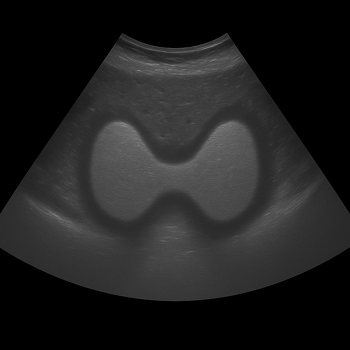

To assess the size and structure of the thyroid gland, for example if there is a suspicion of goiter or nodules in the thyroid gland, you can also supplement with thyroid ultrasound . The ultrasound can see if the gland is enlarged, if there are cysts or nodules and if these need to be followed up further.

What does an enlarged thyroid gland look like?

Many people search for pictures of enlarged thyroid gland images to compare. This is what an enlarged thyroid gland can look like, as a rounded swelling on the lower part of the throat – sometimes this is only visible when swallowing.

The image shows an enlarged thyroid gland.

Remember that a doctor should always assess the appearance. A swollen neck can also be due to other causes, such as enlarged lymph nodes.